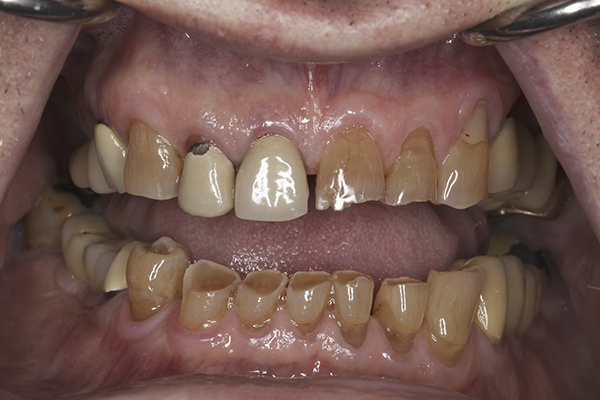

(10.) Preoperative anterior, closed view. Note the end-to-end occlusion of the anterior teeth and the wear on the incisors and centrals resulting in no anterior or canine guidance.

Figure 10